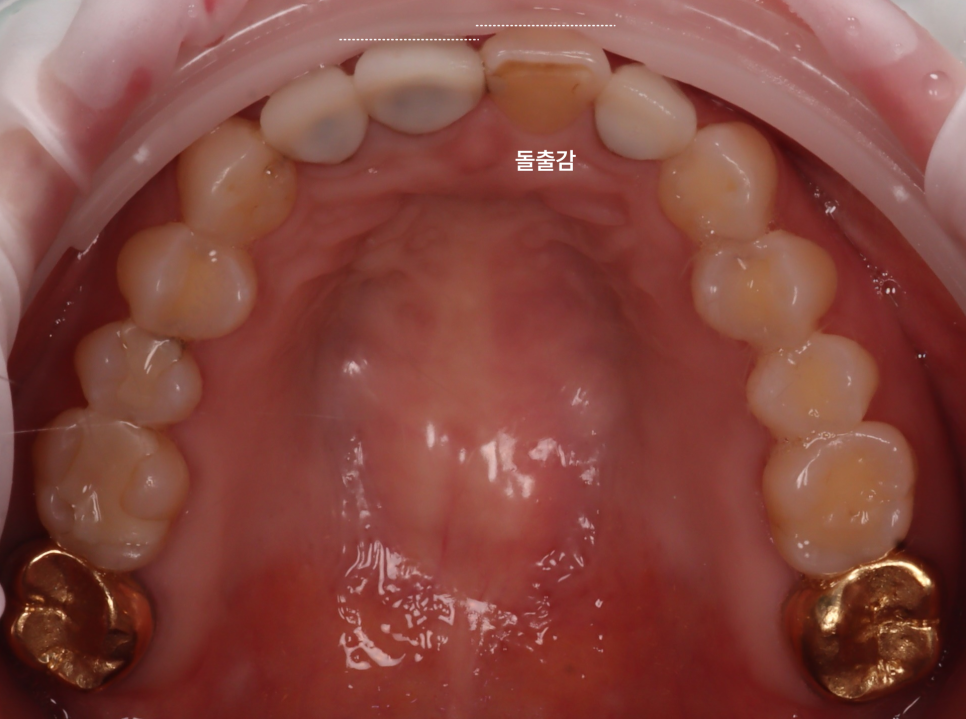

앞니 3개는 크라운이었는데 사이는 원래 치아이다 보니 시간이 지나면서 자연치아의 변색과 마모로 도드라져 보이는 상황이었습니다.

가운데 보철이 안된 치아는 살짝 앞으로 돌출되었더라고요.

이 상태에서 레진으로 덧붙이면 치아를 덜 깎을 수는 있지만 더 튀어나와 보일 수 있어요.